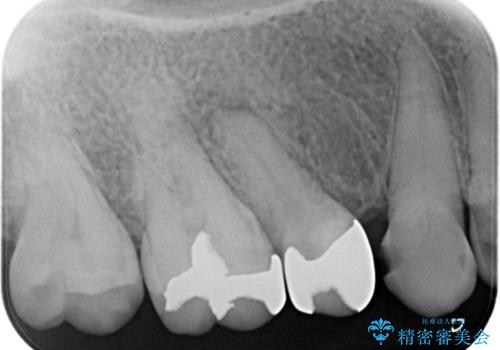

近遠心の辺縁隆線がなくなっている歯は破折抵抗が著しく低下するため、破折防止のためにクラウンを希望されました。